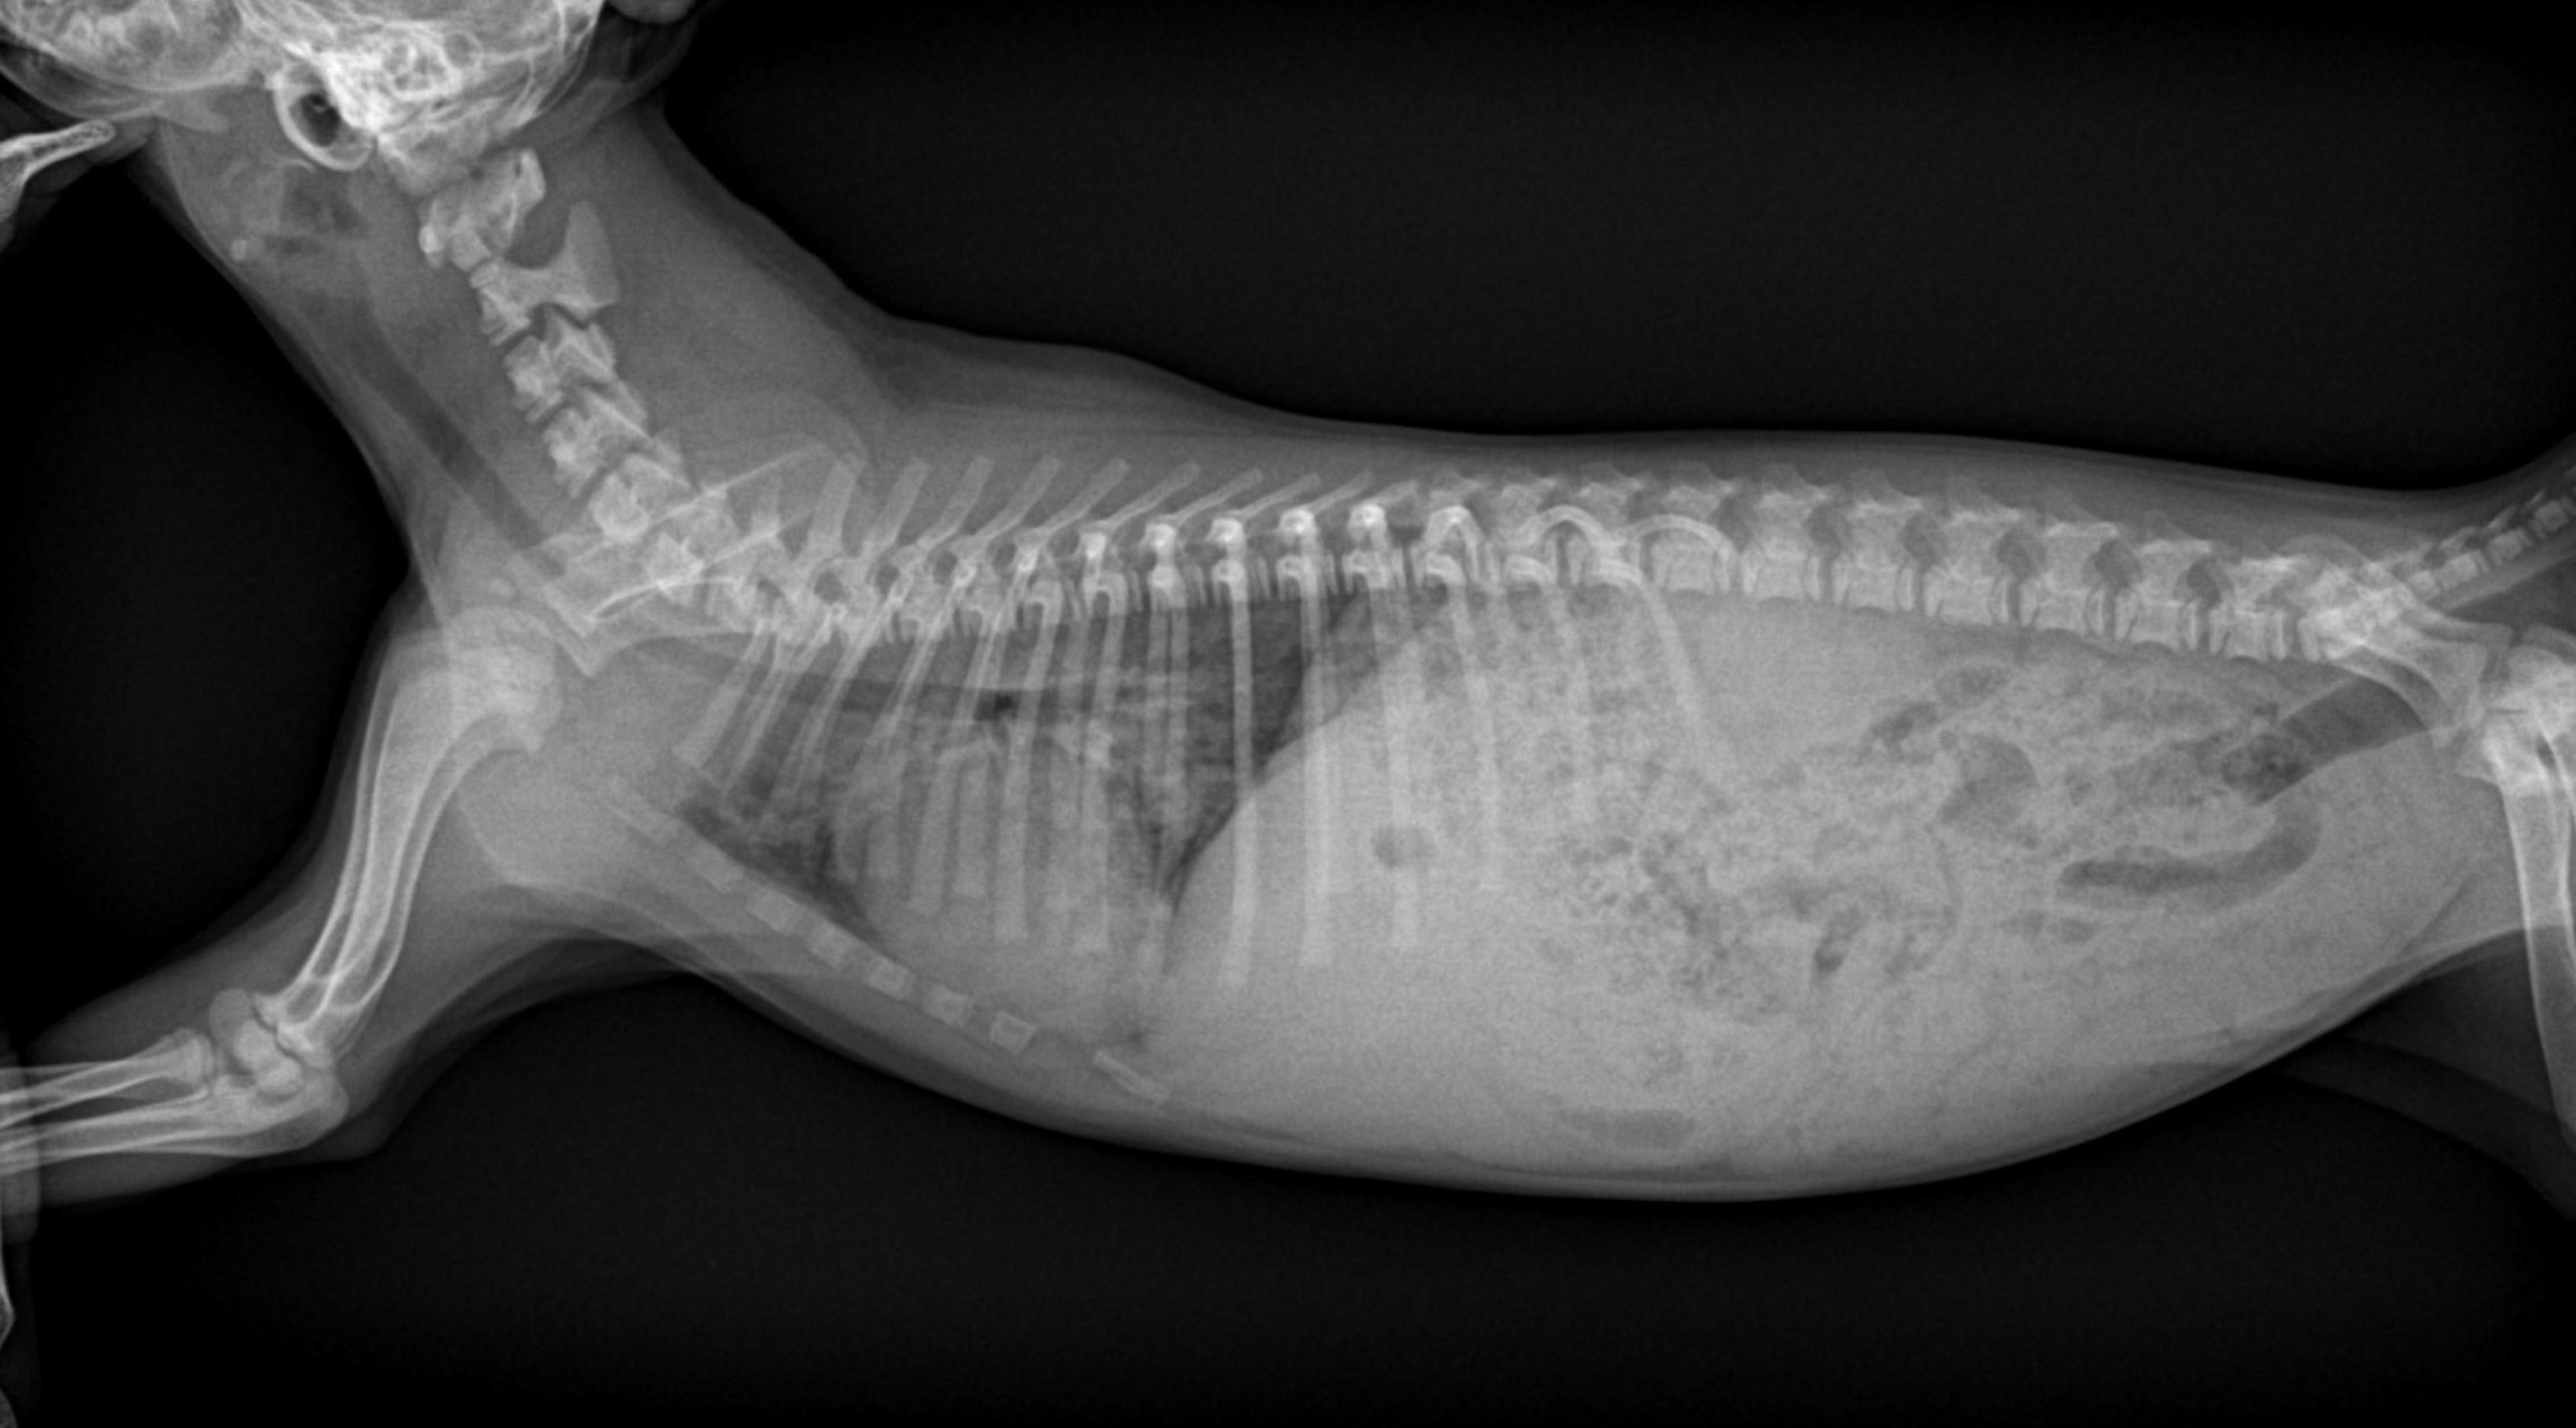

청진상 이상음이 들릴 수 있으며 (쌕쌕거리는 소리, 딱딱거리는 소리, 펑하는 소리 등), 방사선(X-ray) 검사가

진단에 유용합니다.

호흡이 빠르고 열이 있어서 방사선 검사와 혈액 검사를 진행했습니다.

검사결과 백혈구 숫자증가, 염증지표(CRP)의 상승, 방사선상 폐침윤이 확인되어 안타깝게도 폐렴이 진단되었습니다.